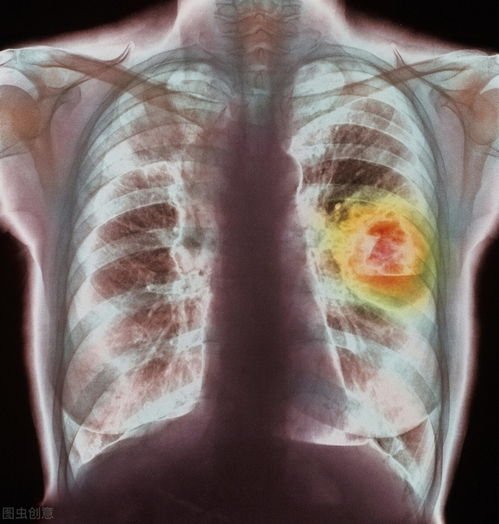

1. 诊断路径:诊断始于详细的体格检查,医生会观察病变形态、大小、质地及与周围组织的关系。组织病理学活检是确诊的金标准,通过取一小块病变组织进行显微镜下检查,可以明确肿瘤类型(绝大多数为鳞状细胞癌)和分化程度。为了明确分期,可能会进行超声、MRI或CT检查,以评估肿瘤侵犯深度、有无海绵体侵犯以及腹股沟、盆腔淋巴结转移情况。